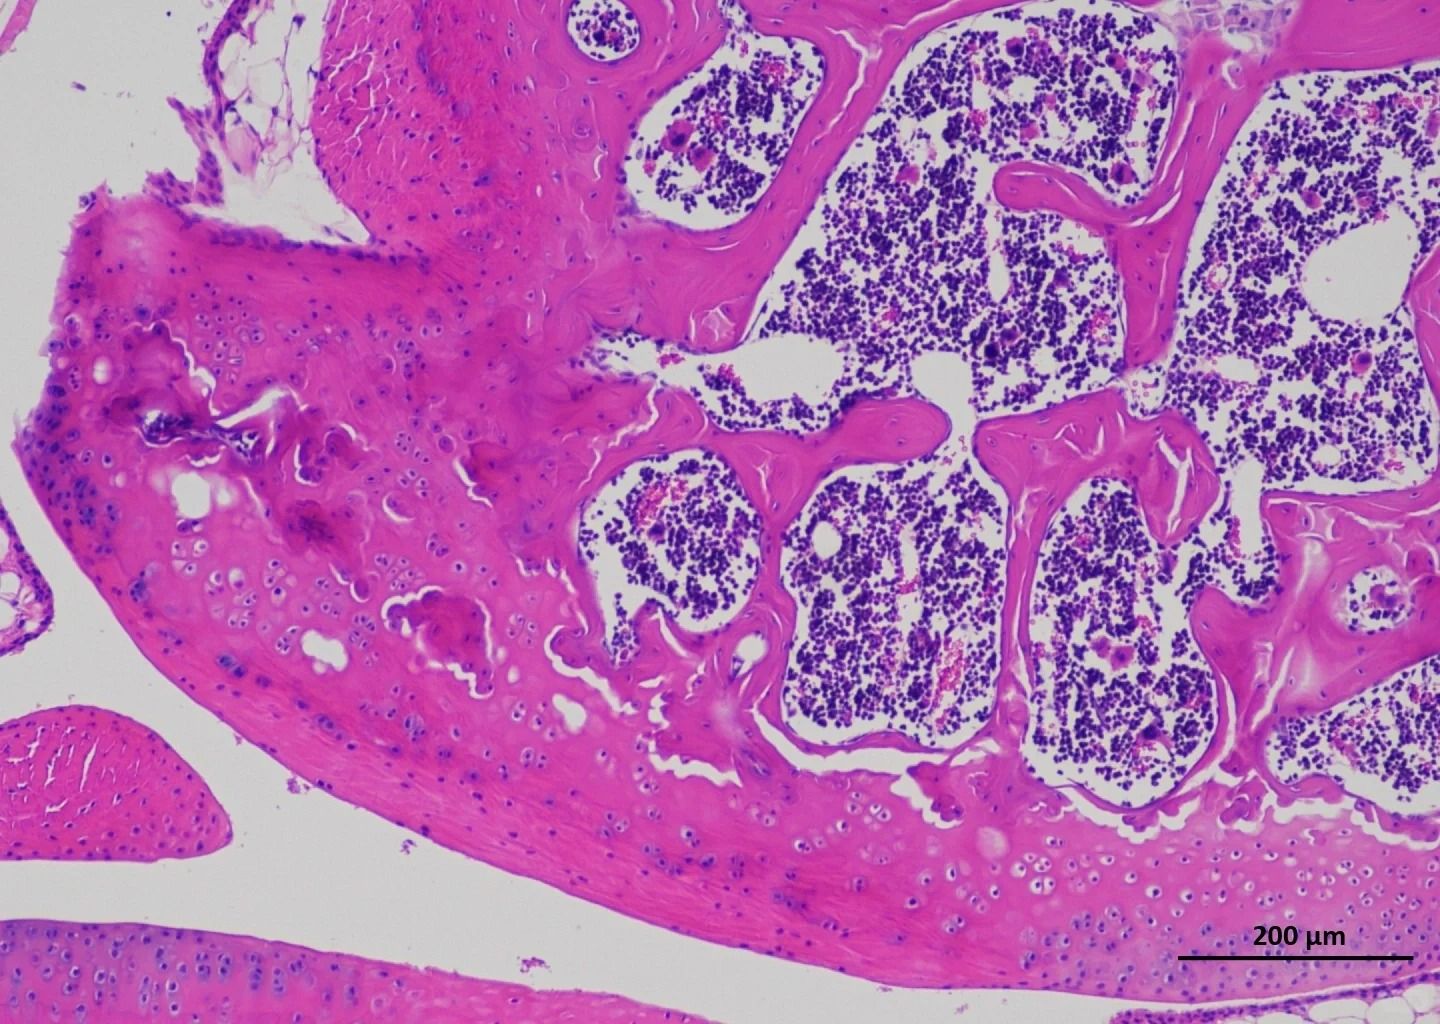

普拉特澤生物承接甲苯胺藍染色等病理染色相關(guān)服務上萬例,積累了操作大量經(jīng)驗,為大家推薦分享甲苯胺藍染色試劑盒

適用場景:常規(guī)組織切片染色(如軟骨、肥大細胞、植物細胞壁等)。

●肥大細胞染色:甲苯胺藍可異染性顯示顆粒,需嚴格控制pH值(酸性條件)。